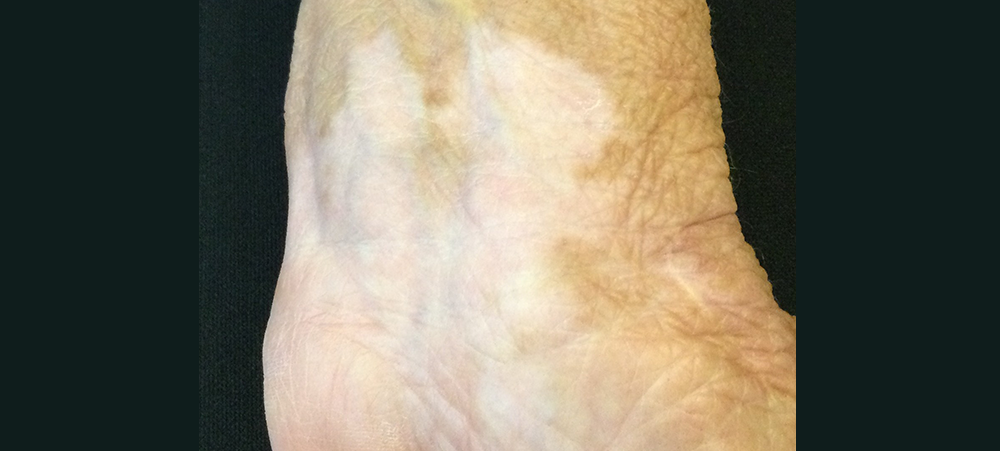

Close-up of vitiligo depigmentation on hand